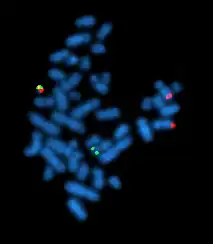

| Cromossomo Filadélfia pelo FISH) | |

Ultimamente, LMC é diagnosticada pela detecção do cromossomo Filadélfia (cromossomo Ph). Esta anormalidade cromossômica característica pode ser detectada pela citogenética, pela técnica de hibridização fluorescente in situ (FISH) ou pela reação em cadeia de polimerase (PCR).[3]

- Citogenética e biologia molecular: Cariótipo: 95% dos casos de LMC são cromossomo Filadélfia positivo (Ph+) e 5% são Ph-; FISH: fusão do Abl e Bcr; reacção em cadeia de polimerase com transcriptase reversa (RT-PCR).